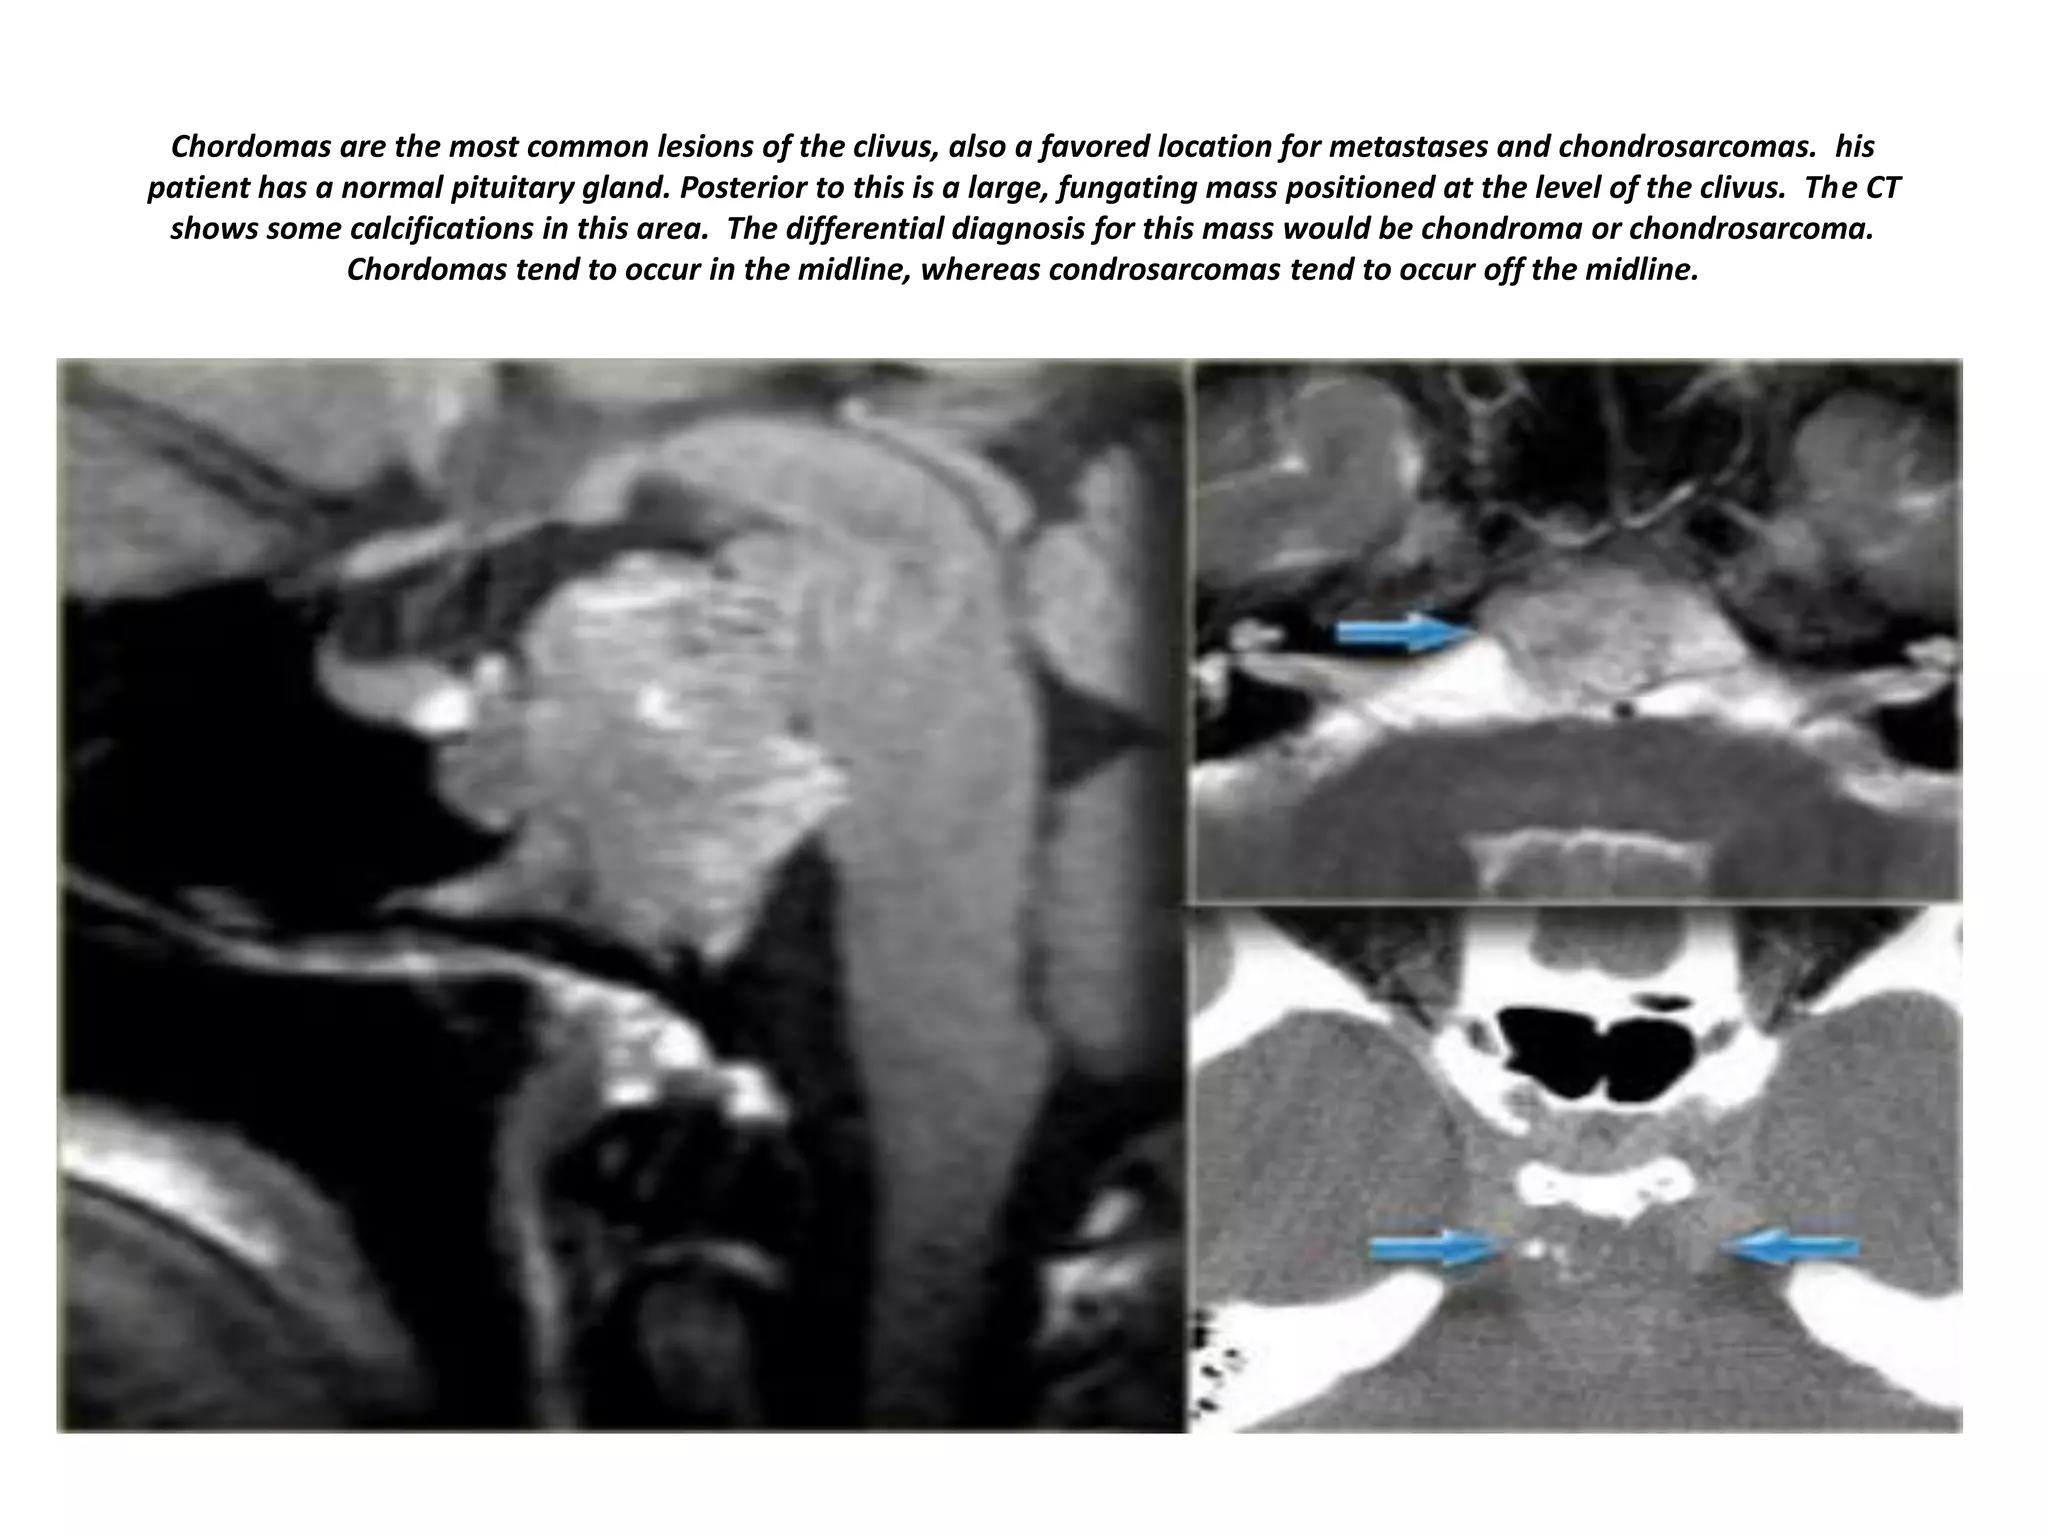

Chordomas are the most common lesions of the clivus, also a favored location for metastases and chondrosarcomas. his

patient has a normal pituitary gland. Posterior to this is a large, fungating mass positioned at the level of the clivus. The CT

shows some calcifications in this area. The differential diagnosis for this mass would be chondroma or chondrosarcoma.

Chordomas tend to occur in the midline, whereas condrosarcomas tend to occur off the midline.